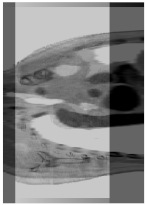

Due to this, an optimized cross-section is formed based on a high-clarity pixel screening strategy, and the pixels of this cross-section are distributed along a curved surface spatially, so the flattened image of this curved cross-section is named “high-quality curved section” (HQCS). Figure 10 shows an example of HQCS. The HQCS is an image, which is supposed to be used in a sequence registration problem as a spatial feature. It can be seen that the HQCS obtained by us containing significant information in the stereo space, which is more effective and accurate than a randomly processed cross section. In the experimental section, we demonstrated that the registration results using HQCS outperformed the traversal registration-based method.

Figure 10.

The diagram of a high-quality curved section (HQCS). (a) is the evaluation map computed by Equation (11), in which the red line is a section curve fitted by the local peak values in evaluation map. (b) is the curved section in the 3D view of the source medical image sequence. (c) is the HQCS used for registration in our work. It is a flattened curved section in the graph (b).